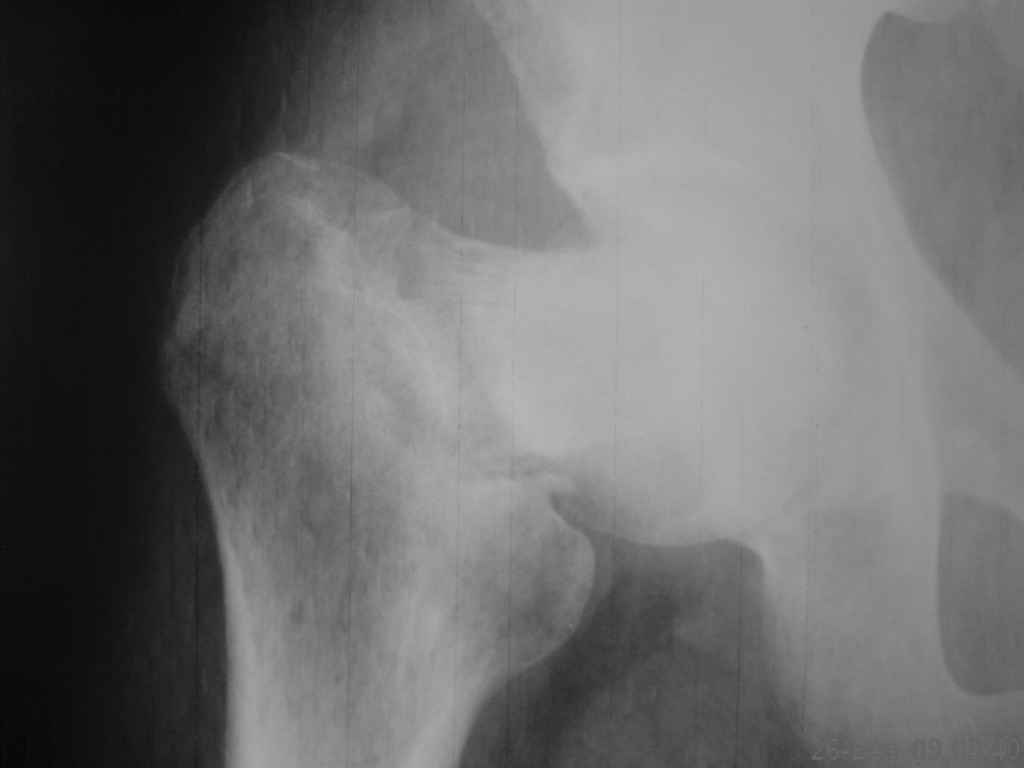

К нам поступил больной,26 лет,травма 6 месяцев назад(падение с

высоты). Лечился консервативно (вытяжение,гипс) по поводу перелома

бедра, перелом шейки был пропущен.

Объективно:ходит с помощью костылей, нога не опорная.Укорочение

приблизительно 6 см, жалуется на умеренные боли при нагрузке в паху и

с/3 бедра.

Ренгенснимки прилагаются(за качество не обессудьте); на КТ с/3 бедра

- формирующийся тугой ложный сустав (извините,не смог представить),

КТ шейки не делали.